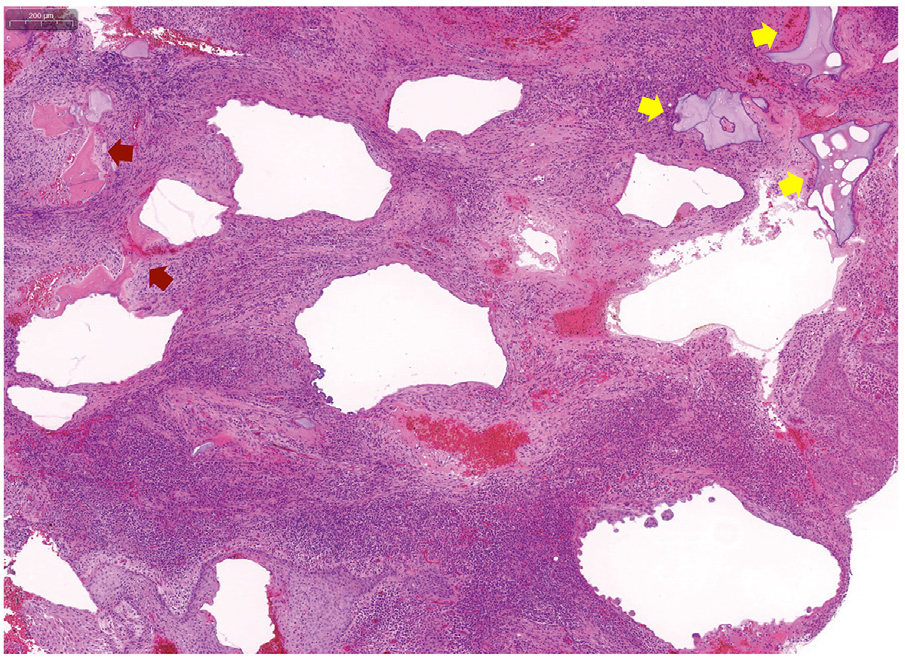

5. Histopathological finding

The retrieved specimens were stained with hematoxylin and eosin. The specimens revealed fibrotic tissue primarily with abundant inflammatory cell infiltration. Small fragments of vital (lacunae and osteocytes) and necrotic bone were observed (Fig. 4).